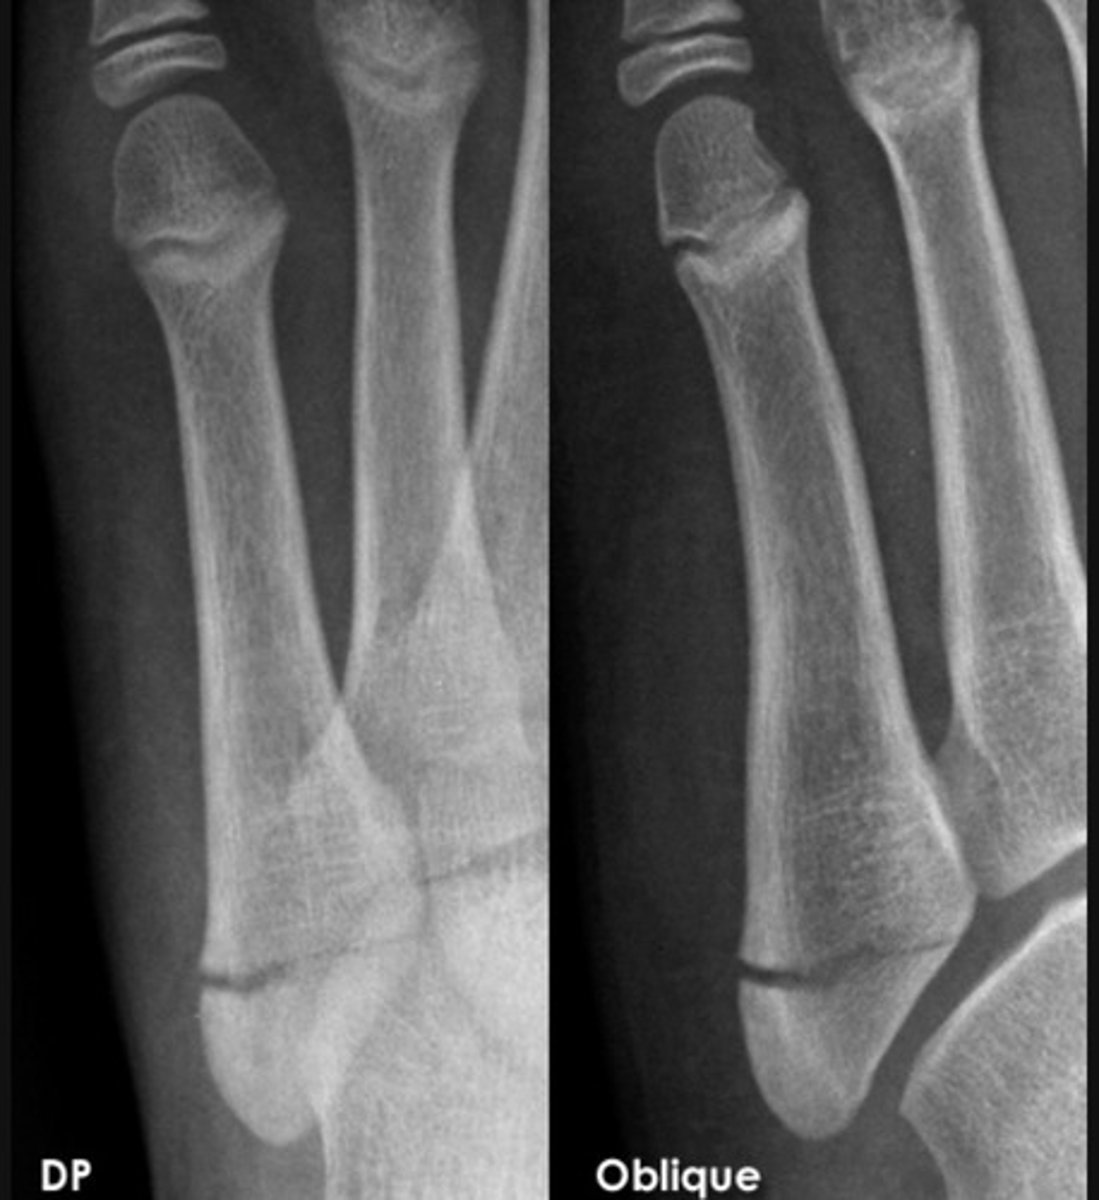

SH type 3

SH 1

SH 4